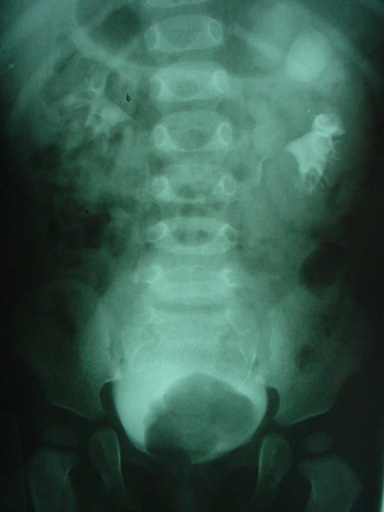

El ureterocele es una dilatación quística de la parte terminal del uréter, que se ubica dentro de la vejiga de la uretra o de ambas. En la mayoría de los casos se acompaña de un doble sistema colector; afecta seis veces más al sexo femenino. En general el tratamiento del ureterocele depende en gran medida del estado del riñón afectado y de la capacidad funcional del riñón contralateral. El espectro de las modalidades terapéuticas incluyen: incisión transureteral del ureterocele, nefrectomía y reconstrucción vesical.

La indicación para procedimiento endoscópico sólo es considerada en el paciente con ureterocele intravesical con un sistema colector simple. En la mayor parte de los pacientes preferimos realizar un reimplante ureteral y resección del ureterocele.